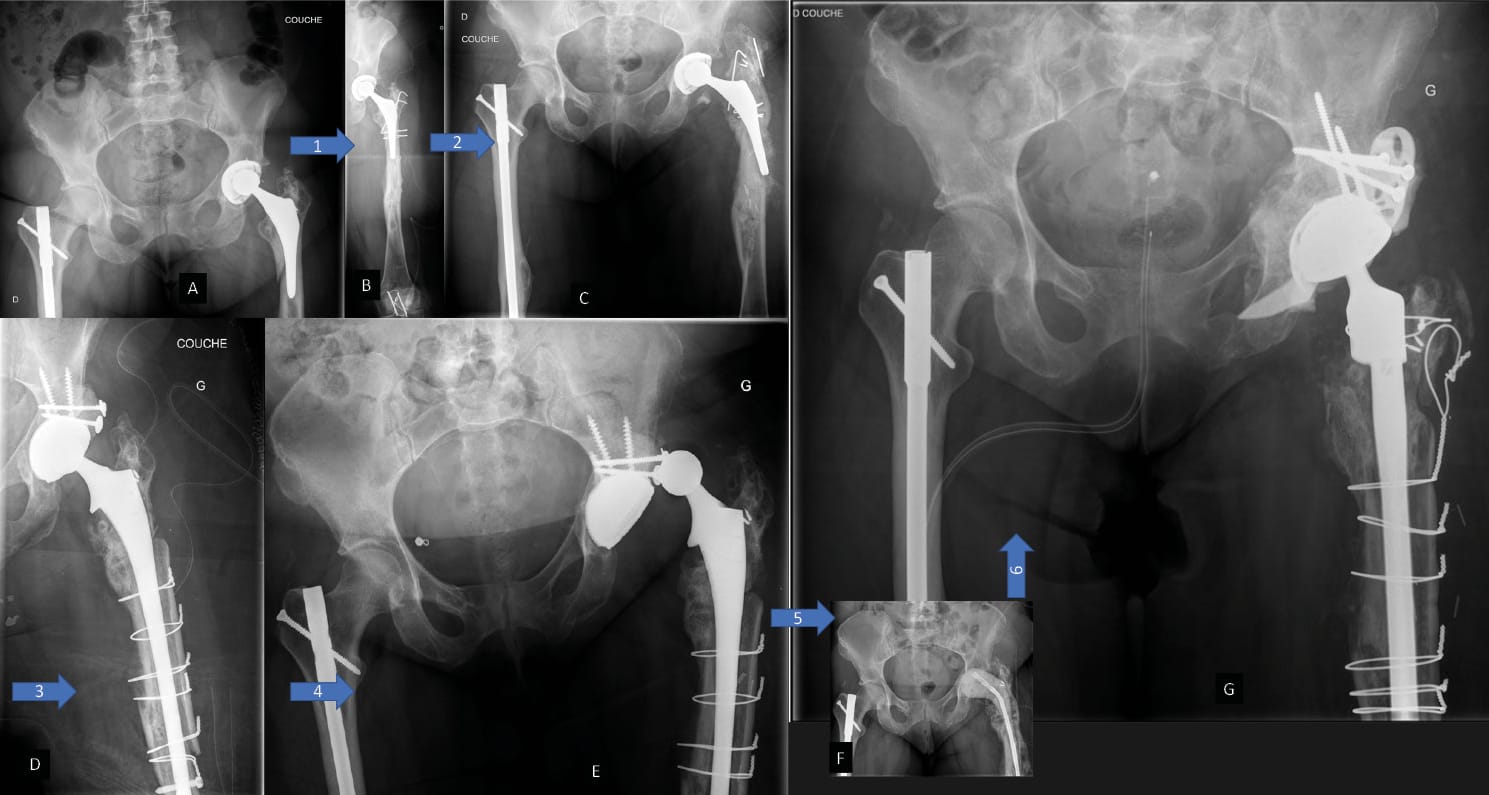

The first option is to use a cementless DM cup either with (Figure 2) or without spikes (Figures 3 and 4) or a peg with a minimum implant size of 40, depending on the manufacturer, and a technically demanding fitting process, resulting in good cup stability for patients with bone defects or poor bone quality, which can, in some cases, leave fewer options. This implant is a first line option indicated particularly in patients with implant instability and moderate bone loss. (Figures 2, 3, 4)

Puget et al. [47] Tricoire J-L, Puget J, Connes H, Canevet G, Moscovici J, Guittard J. Etude anatomique de l’isthme iliaque, base de fixation cotyloïdienne dans les grandes pertes de substance segmentaires lors des reprises de PTH. Morphologie 2004;88:80. https://doi.org/10.1016/S1286-0115(04)98044-7. described the iliac isthmus as an anatomical beam made up of a dense bridge with a potential entry point at the superior-medial and posterior part of the acetabulum. Fixed with a peg (as used with the Integra cup: length 5 cm, diameter 11mm and orientation 55°) inserted into the ilium [48] Desbonnet P, Connes H, Escare P, Tricoire JL, Trouillas J. Total hip revision using a cup design with a peg to treat severe pelvic bone defects. Orthop Traumatol Surg Res 2012;98:346–51. https://doi.org/10.1016/j.otsr.2012.01.006., this implant results in primary stability that allows patients to quickly regain their independence with weight-bearing from the outset. There are various models, both modular and monoblock, on the market today 49. (Figure 5). They can be used in mechanical reconstructions, in cases when a biological reconstruction using bone grafts no longer appears to be suitable.

Another option is the modular dual mobility cup. This type of implant remains useful in cases of moderate bone loss and allows the surgeon to optimise the primary fixations (screws) while still taking advantage of the DM concept. The advantages as well as the potential complications specific to this device have been outlined previously [23] Epinette J-A, Coulomb R, Pradel S, Kouyoumdjian P. Do Modular Dual Mobility Cups Offer a Reliable Benefit? Minimum 5-Year Follow-Up of 102 Cups. J Arthroplasty 2022;37:910–6. https://doi.org/10.1016/j.arth.2022.01.025.. We should also point out the risk of liner malseating, although this does not appear to have an impact on the medium term survival curve [50], Bengoa F, Howard LC, Neufeld ME, Garbuz DonaldS. Malseating of Modular Dual Mobility Liners: High Prevalence in Revision Total Hip Arthroplasty. J Arthroplasty 2023:S0883540323003443. https://doi.org/10.1016/j.arth.2023.03.094.[51], Guntin J, Plummer D, Della Valle C, DeBenedetti A, Nam D. Malseating of modular dual mobility liners. Bone Jt Open 2021;2:858–64. https://doi.org/10.1302/2633-1462.210. BJO-2021-0124.R1.[52] Siljander MP, Gausden EB, Wooster BM, Karczewski D, Sierra RJ, Trousdale RT, et al. Liner malseating is rare with two modular dual-mobility designs. Bone Jt J 2022;104-B:598–603. https://doi.org/10.1302/0301-620X.104B5. BJJ-2021-1734.R1. (Figure 6).

1. With bone-based biological reconstruction (Figure 7)

Nonetheless, bone reconstructions remain a surgical challenge, and all the more so when there is significant bone loss, the patient has undergone multiple operations and there is a context of chronic infection (Figure 8).